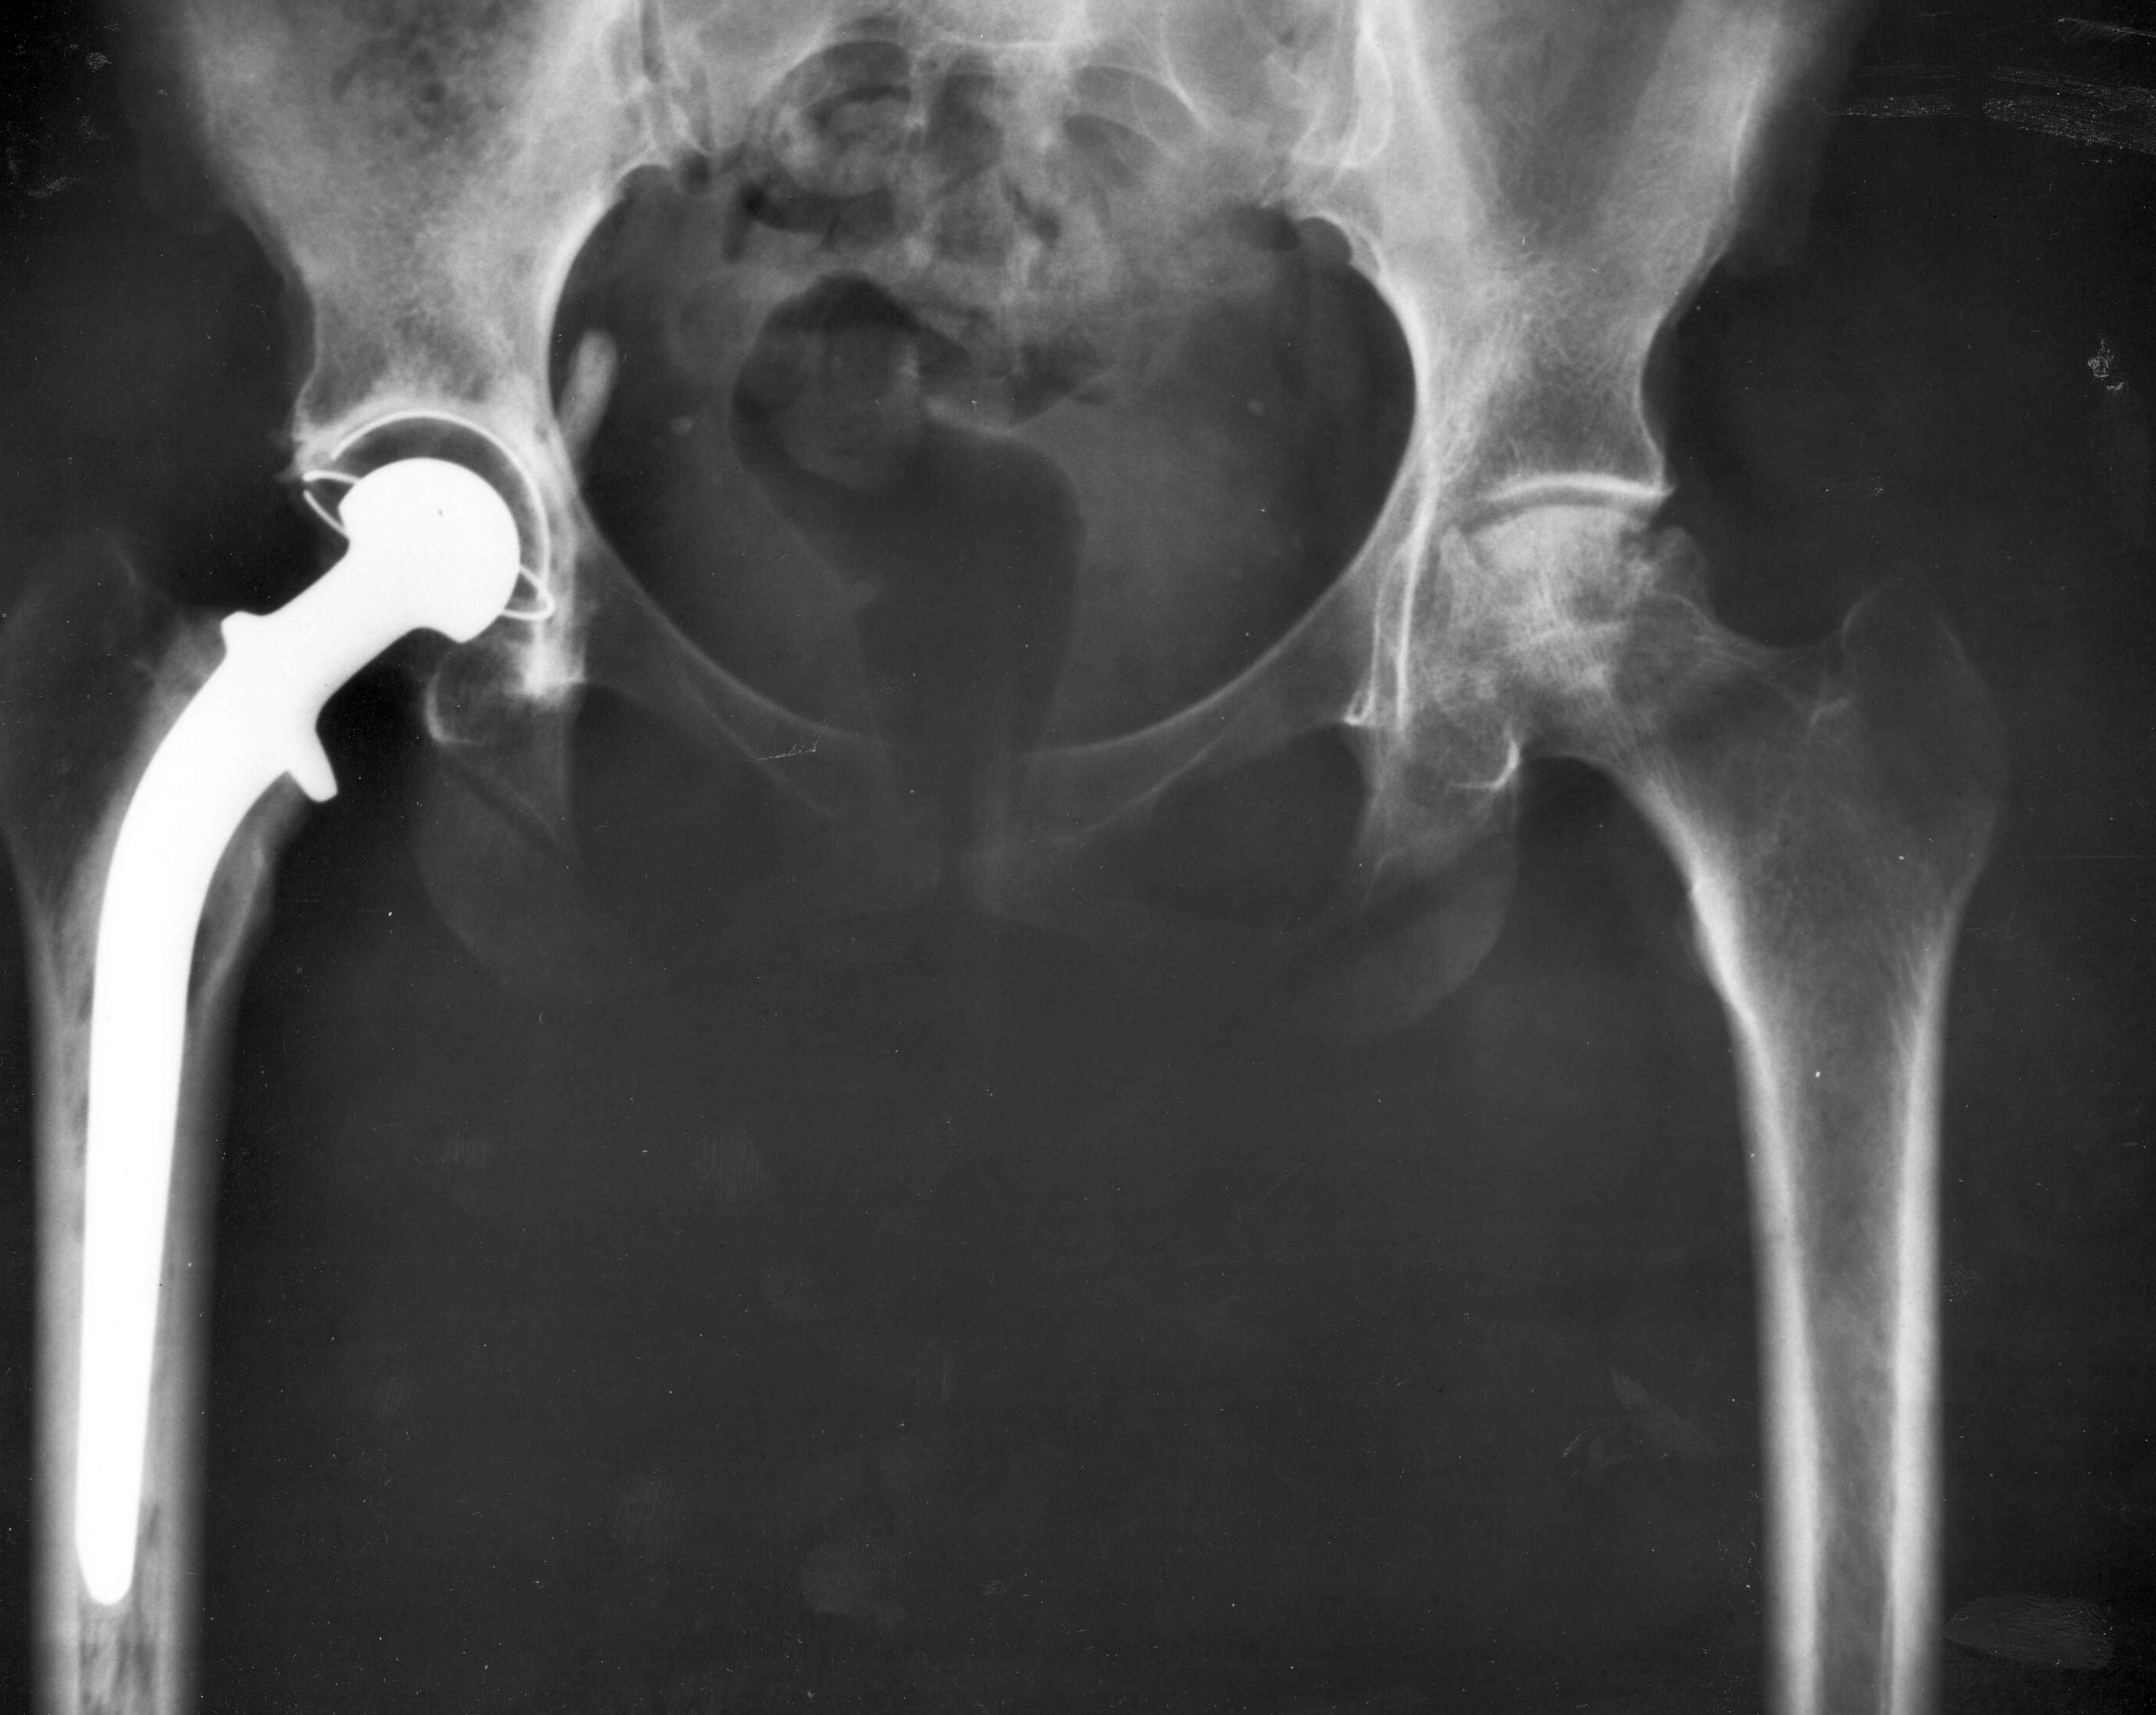

現代髖關節置換壽命延長至25年以上

髖關節問題已成為許多長者日常生活的隱形殺手。根據最新醫學研究,現代髖關節置換手術的耐用性大幅提升,至少可持續25年,甚至達30年之久。

一項發表於權威醫學期刊《刺針》(The Lancet)的系統性回顧與meta分析,分析了來自八個國家關節登記處的近190萬個髖關節置換案例,以及超過5000名患者的臨床研究數據。結果顯示,現代髖關節置換的存活率高達92%可持續至少25年,93%可達20年,甚至有91%的預測可維持30年功能良好。這比起2019年的一項舊研究大幅進步,當時僅58%的舊式植入物能撐過25年。

研究作者Veronica Pentland等專家指出,這得益於過去20年材料科技的躍進,例如使用更耐磨的陶瓷或高度交聯聚乙烯部件,減少了磨損與鬆動風險。雖然整體數據令人鼓舞,但個人結果仍受年齡、健康狀況、骨質密度及手術技巧影響。舉例來說,年輕患者或活躍人士可能需更頻繁監測,以確保植入物長效運作。

這項2026年2月發布的研究迅速引發全球關注,其他相關調查也佐證了這一趨勢。例如,一項2025年美國國家醫學圖書館的研究追蹤超過6萬名患者,發現不到5%在10年內需修復手術,而15%在20年後才需介入。另一項針對50歲以下患者的長期追蹤顯示,使用無水泥固定及陶瓷對陶瓷組合的植入物,10年存活率高達90%,證明現代技術對年輕族群同樣適用。